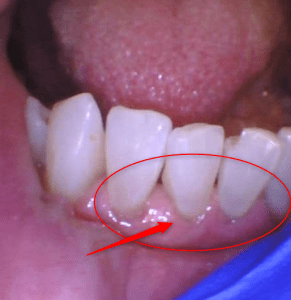

Teeth cleaning: BEFORE AND AFTER

Examine the photos below show teeth before and after cleaning by the hygienist. This tartar buildup was just two months since the cleaning. However, this patient is very prone to tartar buildup. The average person may take many more months to accumulate this amount of tartar. However, a dental hygienist can diagnose your tartar development and prescribe the frequency of having your teeth cleaned.